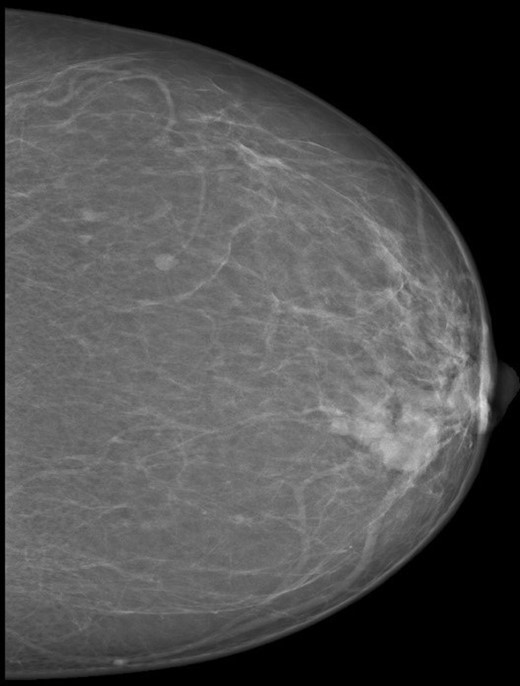

A 55-year-old mother presented to the breast clinic with left breast lump for the past two weeks. Physical examination revealed a 3×2 cm solitary hard mass located at the left inner upper quadrant, with no palpable axillary lymph nodes. There was no skin changes or nipple discharge. Mammogram showed a 3.2 cm round high density mass in the inner upper quadrant of the left breast. No micro calcifications noted (Fig. 1). Ultrasound guided fine needle aspiration (FNAC) demonstrated features consistent with breast carcinoma.

Mammogram picture of left breast showing a lobulated poorly define mass m 3 × 2 × 2.2 cm.